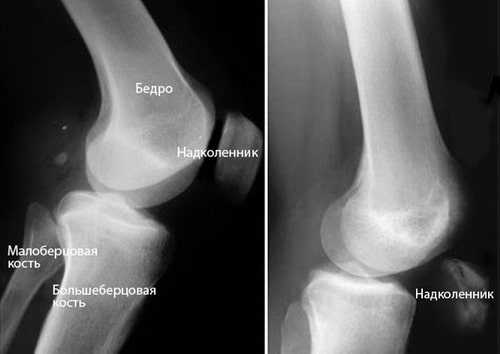

Рентгенография. При разрыве сухожилия четырехглавой мышцы надколенник смещается вниз относительно своего нормального положения, что очень хорошо видно на рентгенограмме в боковой проекции. Для подтверждения диагноза полного разрыва этой рентгенограммы обычно бывает достаточно.

(Слева) Нормальное положение надколенника на рентгенограмме в боковой проекции. (Справа) Смещение надколенника вниз при разрыве сухожилия четырехглавой мышцы.

Рентгенография. Диагностика по методике рентгенографии позволяет визуализировать не только полное разделение сухожилия, но и патологическое смещение коленной чашечки вниз.

На изображении слева (в боковой проекции) можно увидеть нормальное положение коленной чашечки. Изображение справа показывает характерное при разрывах сухожилия смещение надколенника вниз.